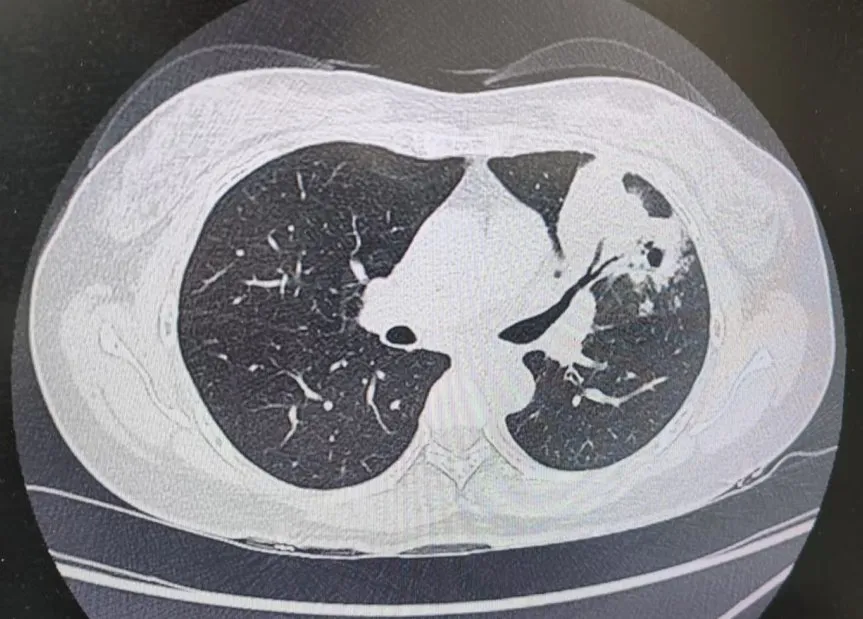

患者肺部CT影像

“一般來說,肺炎經(jīng)過一周的抗感染治療,病灶會有所吸收。但陳女士的肺部陰影紋絲不動,這種情況必須提高警惕。”宋剛主任團隊立即啟動了更深入的“三部精準診斷”程序:

3、CT引導(dǎo)下穿刺活檢:病理診斷為左肺上葉腺癌。

肺炎型肺癌,因其影像學(xué)表現(xiàn)與普通肺炎極為相似,臨床上誤診率極高。然而確診僅是第一步。宋剛主任當天即召集腫瘤科、病理科、影像科等多學(xué)科專家會診,為陳女士制定個體化治療方案。